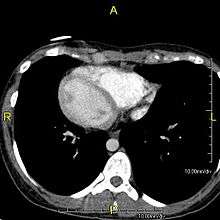

Axial CT image showing dextrocardia and situs inversus in a patient with Kartagener syndrome.

If the heart is swapped to the right side of the thorax, it is known as "situs inversus with dextrocardia" or "situs inversus totalis". If the heart remains on the normal left side of the thorax, a much more rare condition (1 in 2,000,000 of the general population), it is known as "situs inversus with levocardia" or "situs inversus incompletus".